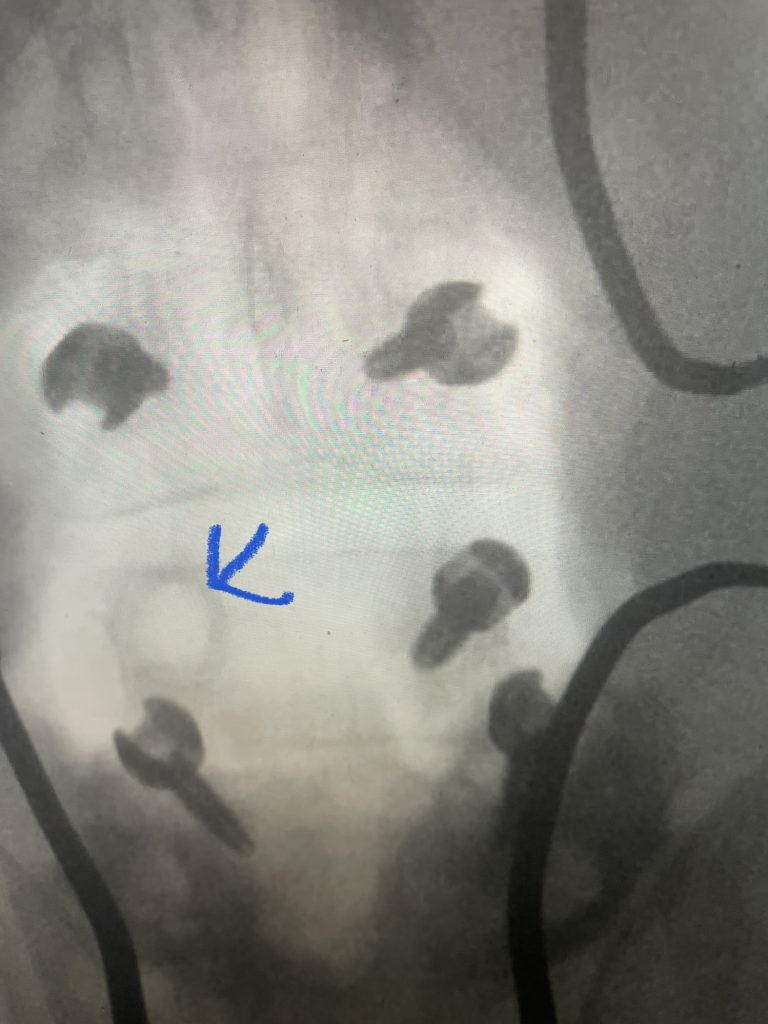

The patient also had a retrolisthesis at L3-4 with mild stenosis. It was also noted that he had lucencies around the L4 screws, suggesting a pseudoarthrosis at L4-5. which is a lack of bony fusion (Fig 6). Patient was had failed conservative management and was taken to the operating room where his construct was explored. There was a complete lack of bony fusion mass between L4 and L5 and the screws were loose. Interestingly the L5-S1 region had a solid bony fusion where we had used BMP, but the L4-5 region did not. We removed the construct and removed the remnant of L4 lamina and the inferior processes and decompressed from L3 to to L5, decompressing well the L4 and L5 nerve roots. We placed new instrumentation from L3-5 with the use of BMP which was discussed with the patient prior to surgery (Fig 7). We also felt it was necessary because of the failure of the fusion. Post operatively the patient had an uneventful course with significant improvement of his prior symptoms.

Fig 7: Intraoperative fluoroscopic AP image of the new construct from L3-5. Note the very large lucency around prior L4 screw